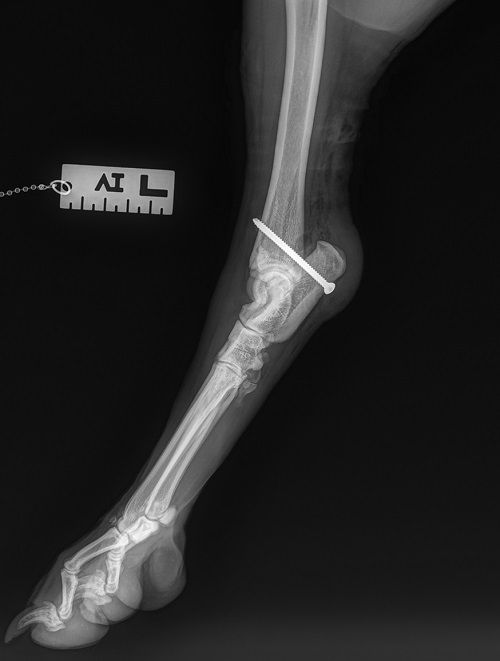

Beim Einsatz einer calcaneotibialen Schraube wird eine Bohrung von der plantaren Seite des Calcaneus unter Schonung der Beugesehne mit Bohrrichtung nach kraniomedial zur distalen Tibia durchgeführt und folgend eine Positionsschraube eingesetzt ([Abb. 4]).